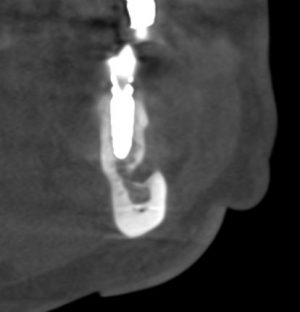

Посмотрим на результат:

особенно на то, что внутри:

Обратите внимание, что между пересаженным костным блоком и принимающим ложем нет чёткой границы, а сам регенерат по цвету и структура, практически, не отличается от альвеолярного гребня. Это как раз то, что я называю хорошим результатом остеопластической операции. Нам останется только сформировать десну и установить коронки на интегрированные имплантаты.

Но, насколько долговечен подобный результат остеопластики? Посмотрим на КЛКТ через 18 месяцев:

или

Как видите, даже структурно регенерат не отличается от подлежащего альвеолярного гребня, хотя заметен на снимке своей неестественной формой. Это говорит о том, что результат остеопластической операции стабилен, и мы можем быть спокойны за дальнейшую судьбу имплантов.